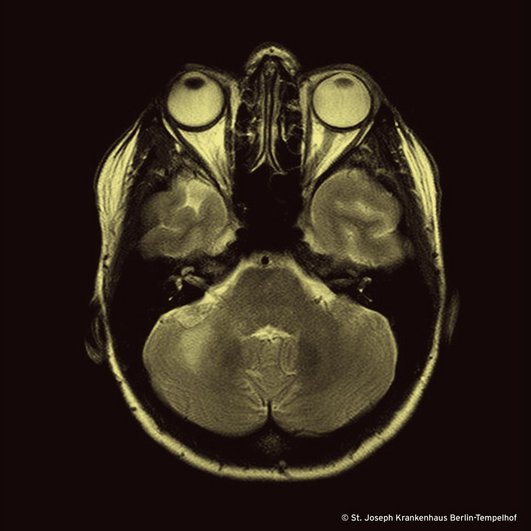

Unser Bild zeigt eine Kernspinntomographie einer 47 Jahre alten Frau ohne bekannte Vorerkrankungen, die sich im Dezember 2020 mit einer subakut aufgetretenen, schmerzlosen, dystonen Feinmotorikstörung der rechten Hand vorstellte. Wegen des radiologischen Befundes und des Nachweises von oligoklonalen Banden im Liquor wurde die Verdachtsdiagnose „Multiple Sklerose“ gestellt. Die Patientin wurde daraufhin mit Glucocorticoiden behandelt. Im kurzfristigen Verlauf entwickelte sie darunter ein Taubheitsgefühl des rechten Gesichts, Kribbelparästhesien des linken Arms und eine deutliche Verschlechterung des Ganges. Sie war nur noch wenige Schritte gehfähig bei fortbestehend schwerwiegender Koordinationsstörung der rechten Körperhälfte. Insgesamt verschlechterte sich ihr Zustand kontinuierlich und dramatisch.

Die Untersuchung einer Kleinhirnbiopsie war zunächst inkonklusiv. Erst mit der nachgereichten fokussierten Fragestellung konnte die Diagnose PML gestellt werden. Die Patientin hatte eine bis dahin undiagnostizierte HIV-Infektion. Im Bild sieht man eine PML-Manifestation im Marklager des rechten lobus posterior cerebelli.